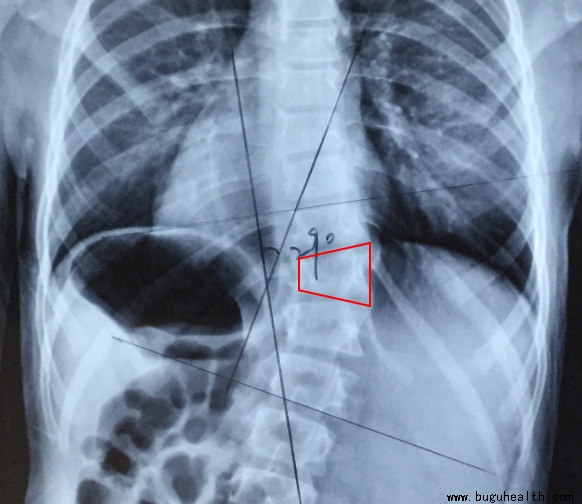

以下患儿,虽然已经穿戴支具3年,但因骨骼生长没有闭合,且仍然有残存度数,所以,需要继续穿戴。